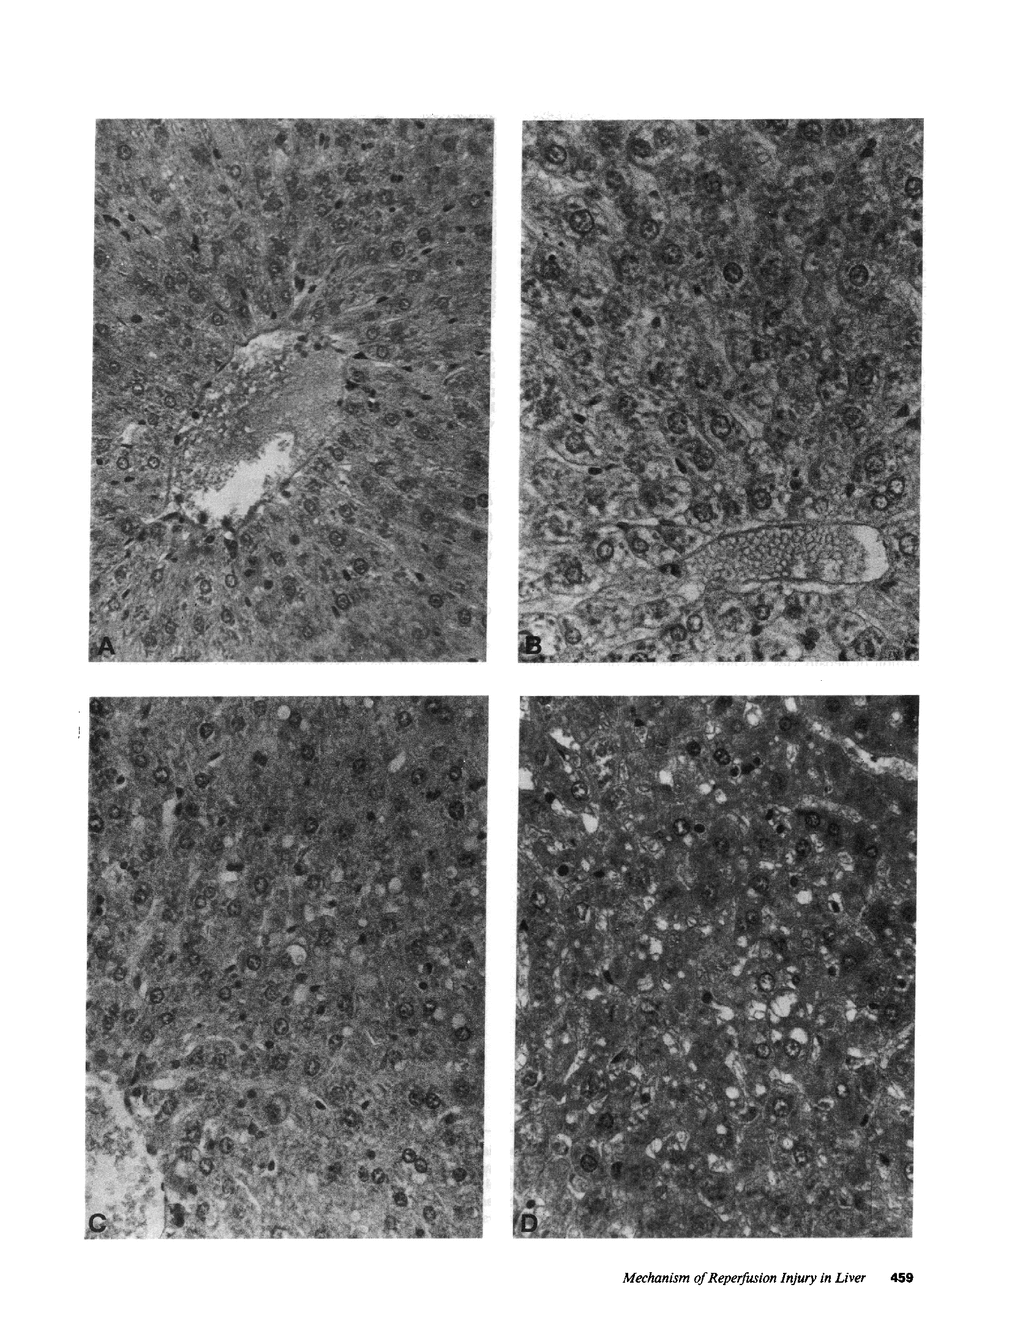

The time course of oxidative stress and tissue damage in zonal liver ischemia-reperfusion in rat liver in vivo was evaluated. After 180 min of ischemia, surface chemiluminescence decreased to zero, state 3 mitochondrial respiration decreased by 70-80%, and xanthine oxidase activity increased by 26% without change in the water content and in the activities of superoxide dismutase, catalase, and glutathione peroxidase. After reperfusion, marked increases in oxyradical production and tissue damage were detected. Mitochondrial oxygen uptake in state 3 and respiratory control as well as the activities of superoxide dismutase, catalase, and glutathione peroxidase and the level of nonenzymatic antioxidants (evaluated by the hydroperoxide-initiated chemiluminescence) were decreased. The severity of the post-reperfusion changes correlated with the time of ischemia. Morphologically, hepatocytes appeared swollen with zonal cord disarrangement which ranged from mild to severe for the tissue reperfused after 60-180 min of ischemia. Neutrophil infiltration was observed after 180 min of ischemia and 30 min of reperfusion. Mitochondria appear as the major source of hydrogen peroxide in control and in reperfused liver, as indicated by the almost complete inhibition of hydrogen peroxide production exerted by the uncoupler carbonylcyanide p-(trifluoromethoxy) phenylhydrazone. Additionally, inhibition of mitochondrial electron transfer by antimycin in liver slices reproduced the inhibition of state 3 mitochondrial respiration and the increase in hydrogen peroxide steady-state concentration found in reperfused liver. Increased rates of oxyradical production by inhibited mitochondria appear as the initial cause of oxidative stress and liver damage during early reperfusion in rat liver.